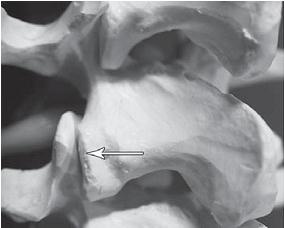

Таким образом, мы вкратце рассмотрели отделы позвоночного столба — этой удивительной конструкции, которая оптимально приспособлена для вертикального положения тела, работает чётко и слаженно. Но это, так сказать, обзор в целом. Теперь хотелось бы обратить ваше внимание на любопытные подробности из той же области остеологии (учение о костях), касательно важных элементов опорно-двигательного аппарата. Позвоночник человека — орган сегментарный (слово «сегмент» произошло от латинского слова segmentum — «отрезок»). Он состоит из отдельных позвонков, расположенных между ними межпозвонковых дисков, а также связок, суставов. Позвонок Итак, одним из основных элементов позвоночника является позвонок (vertebra). По своему строению типичный позвонок напоминает костяной перстень, состоящий из массивного тела позвонка (в нашем случае имитирующий большой драгоценный камень в этом кольце), дуги (точнее двух полудужек, соединяющихся сзади и образующих остистый отросток), замыкающей позвоночное отверстие. Данные отверстия, соединяясь, образуют позвоночный канал, где располагается спинной мозг. На дуге «кольца» имеется 7 по-своему интересных, анатомически выразительных отростков: это остистый отросток, два поперечных и четыре суставных отростка (два верхних и два нижних). В эту схему не вписываются только два верхних шейных позвонка (атлант и эпистрофей), крестцовые позвонки (из-за слияния в единую кость, их видоизменение) и рудиментарные копчиковые позвонки, которые, как мы уже выяснили, из-за особенностей отличаются своим строением от описанной схемы. У основания дуги имеется верхняя и нижняя позвоночные вырезки, которые при соответствующем соединении двух соседних позвонков образуют межпозвонковые отверстия. Тела позвонков приспособлены к тому, чтобы нести на себе тяжесть туловища, и являются основными опорными структурами позвоночника. ![]() Рисунок № 15. Образное сравнение позвонка и перстня Не случайно я сравнил тело позвонка с драгоценным камнем. Это действительно драгоценный по функциям элемент позвонка. Дело в том, что тело позвонка состоит из губчатого вещества пористой структуры, которое образовано отдельными костными перекладинами — трабекулами (лат. trabecula — небольшая балка, перекладина), основой микроскопичного строения которых являются костные пластинки. Ячейки губчатого вещества тела позвонка заполнены красным костным мозгом. А красный костный мозг, как известно, это важнейший орган кроветворения и костеобразования, поскольку в его тканях находятся кроветворные элементы (стволовые клетки), клетки, разрушающие кость (остеокласты) и клетки, образующие кость (остеобласты). Ценность заключается в том, что именно от тела позвонка поступает регулярное и единственное питание для межпозвонкового диска через замыкательную (гиалиновую) пластинку, отделяющую губчатую кость тела позвонка от межпозвонкового диска. О питании межпозвонкового диска мы будем говорить ещё не раз, поскольку это является существенным моментом в понимании причин возникновения и развития многих заболеваний позвоночника. А пока хочу привести наиболее доходчивое сравнение. Жизненно важное питание, поступающее от тела позвонка, представляет собой для межпозвонкового диска практически то же, что, к примеру, в Великую Отечественную войну представляла собой «Дорога жизни» для жителей блокадного Ленинграда (ныне Санкт-Петербурга). Ладожское озеро было тогда, подобно замыкательной пластинке, единственной транспортной магистралью, через которую поступало продовольствие для города. Поскольку мы уж коснулись темы Великой Отечественной войны, то приведу и другое, на сей раз весьма печальное сопоставление. Общеизвестный факт, как в концентрационных лагерях во время войны людей заставляли тяжело работать и при этом плохо кормили, вследствие чего доводили их до полного истощения, результатом которого зачастую была смерть. Аналогичный процесс происходит и в межпозвонковом диске. То есть, клеточки межпозвонкового диска, систематически испытывая значительные нагрузки и при этом не получая должного питания (а это происходит, к примеру, когда человек много сидит и мало ходит), истощаются и умирают, что соответственно со временем сказывается на диске в целом. ![]() Фото № 2. Наблюдается пористая структура тела позвонка в разрезе Но вернёмся к нашему перстню. О «драгоценном камне» — теле позвонка — у нас уже есть общее представление. Теперь полюбуемся отростками, расположенными на дуге. Поговорим о четырёх суставных отростках позвонка (двух верхних и двух нижних), за счёт которых позвонки соединяются с выше - и нижележащими позвонками. Кстати, соединяясь, нижние суставные отростки вышележащего позвонка и верхние суставные отростки нижележащего позвонка образуют дугоотростчатые суставы, так называемые истинные синовиальные суставы. Как вы знаете, суставом как таковым, именуют подвижное соединение костей скелета (позволяющее им перемещаться друг относительно друга), принимающее участие в осуществлении опорной и двигательной функций. Наряду с истинными суставами имеются полусуставы (по-научному межпозвонковые симфизы; symphysis — «переходные соединения»), к которым относятся и межпозвонковые диски. МРТ № 4 ![]() МРТ № 5 ![]() На МРТ № 4 наблюдается межпозвонковый диск в начальной стадии развития дегенеративно-дистрофического процесса. На МРТ № 5 наблюдается межпозвонковый диск на более поздней стадии развития дегенеративно-дистрофического процесса. ![]() Фото № 3. На фото макета позвоночника стрелкой указан дугоотростчатый сустав позвоночника. Дугоотростчатые суставы имеют синовиальную оболочку, фиброзную капсулу, суставную полость с синовиальной жидкостью, связки. Каждый дугоотростчатый сустав покрыт гиалиновым хрящом, по краю которого (на расстоянии 2–4 мм от края сочленяющихся поверхностей) прикрепляется капсула сустава. Изнутри суставная капсула покрыта синовиальной оболочкой. По передней поверхности она покрыта желтой связкой и составляет заднюю поверхность межпозвонкового отверстия. Капсула усиливается дорсально за счёт многораздельных мышц и вентрально жёлтой связкой, которая вплетается в неё в верхнемедиальном отделе. Верхний суставной отросток лежащего ниже позвонка массивнее нижнего и расположен больше кпереди и кнаружи, а нижний — кзади и кнутри. Часть верхнего суставного отростка у корня дуги участвует в формировании бокового углубления позвоночного канала. |